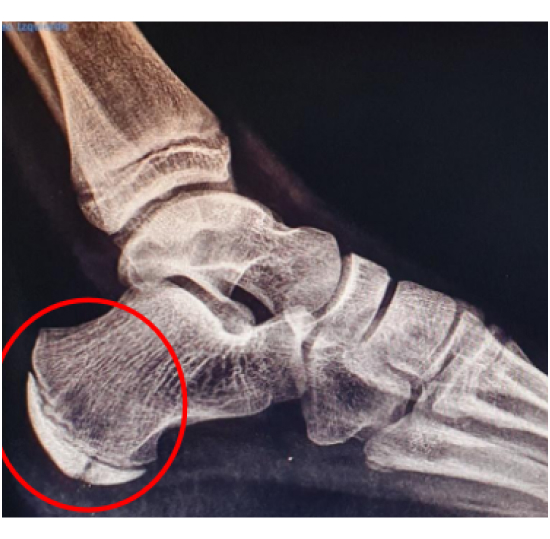

En las osteocondrosis (osteocondritis) nos encontramos ante la inflamación del cartílago articular más su hueso subcondral y centros de osificación de huesos por una insuficiencia del aporte sanguíneo de manera normalmente reversible en estas zonas, dándose especialmente en niños. Suele aparecer dolor en la zona, especialmente por la presión e imposibilidad de andar o realizar deporte. Un tratamiento adecuado y rápido reduce el periodo de recuperación y posibles complicaciones.

En la imagen vemos un SERVER u osteocondrosis en el calcáneo.